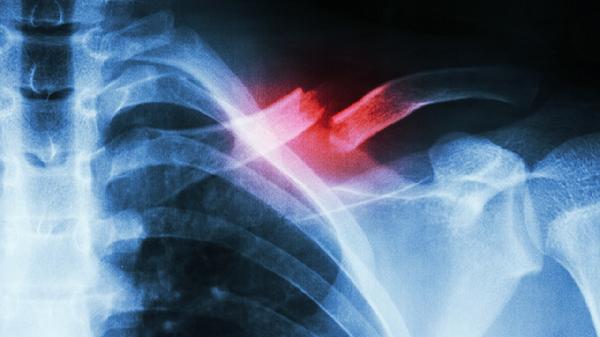

多发性肋骨骨折有哪些典型症状

多发性肋骨骨折的典型症状主要有局部疼痛、呼吸受限、反常呼吸运动、皮下气肿、咯血等。多发性肋骨骨折通常由外力撞击、骨质疏松、肿瘤转移等因素引起,严重时可导致血气胸或肺挫伤,需紧急就医处理。

骨折端刺破肺组织后,空气经裂口进入皮下组织形成捻发感。常见于锁骨上窝或胸壁,严重时可蔓延至颈部及面部。需警惕张力性气胸可能,X线检查可明确气体扩散范围,必要时行胸腔闭式引流。